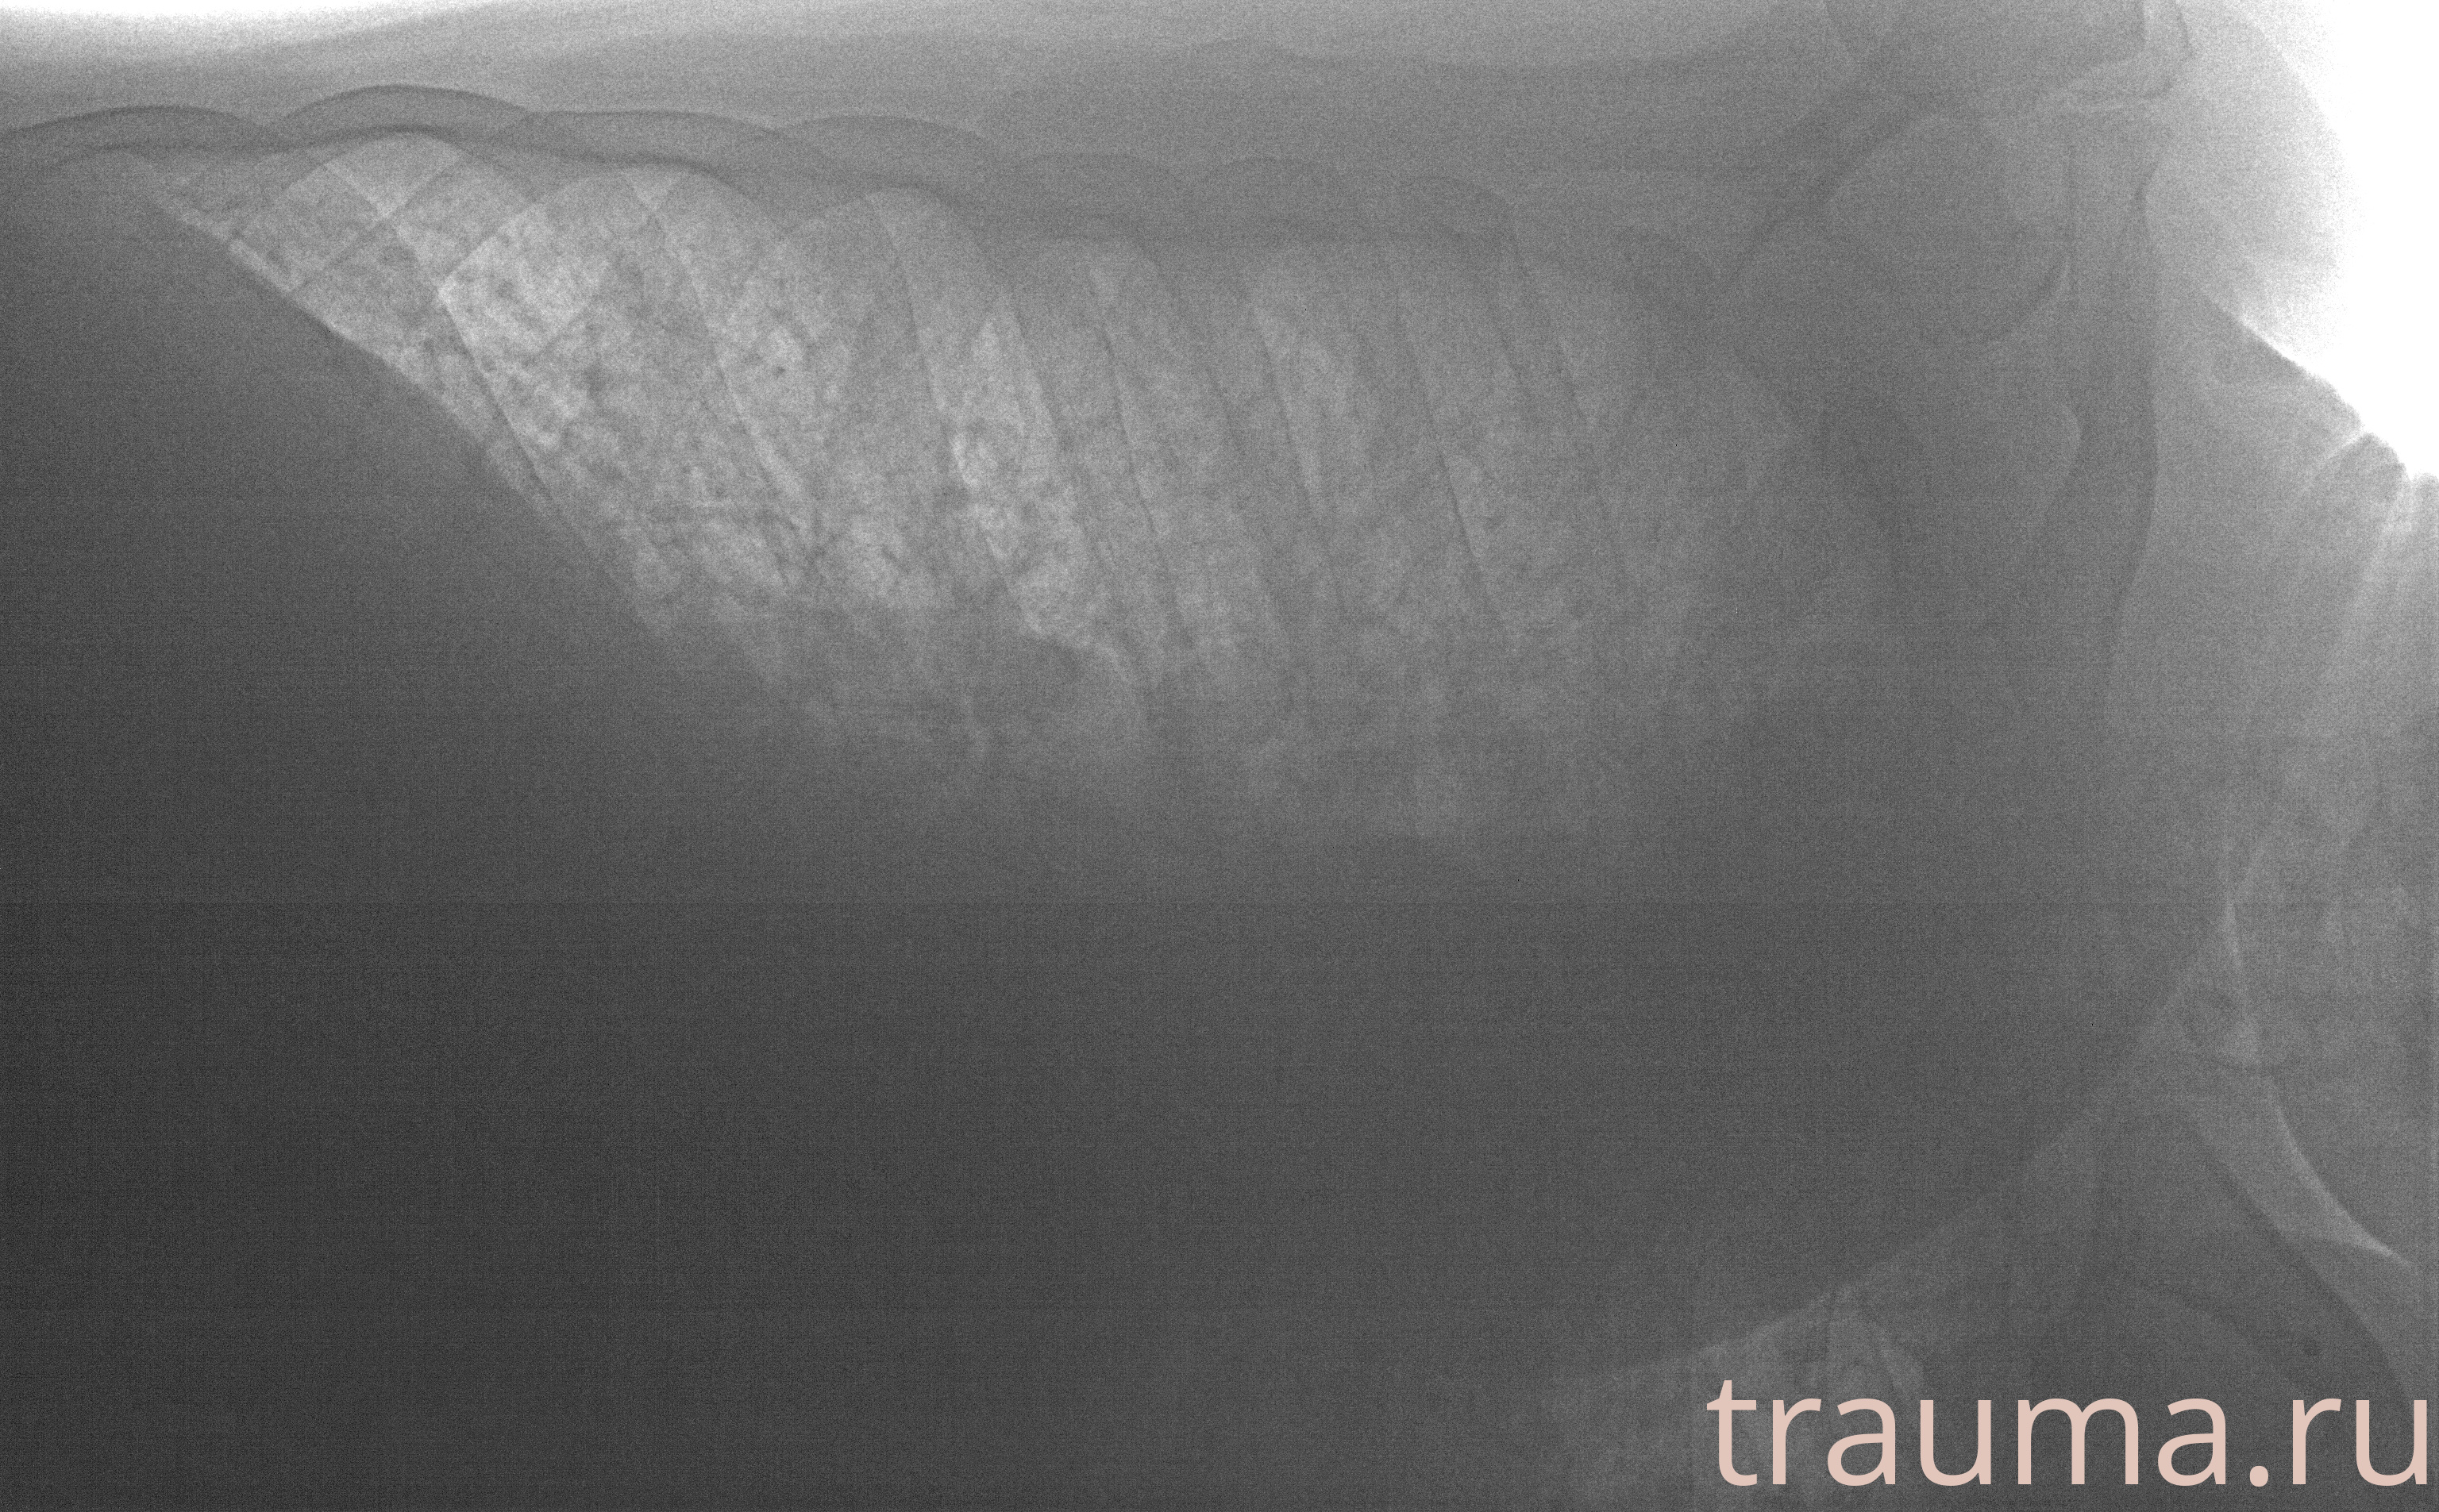

Рентгенограммы

Рентген на дому: по вашему адресу приезжает врач-рентгенолог, травматолог-ортопед с мобильным рентгеновским аппаратом, проводит диагностику травмы или заболевания, делает необходимые рентгенограммы, дает рекомендации по дальнейшему лечению. Получить качественные снимки в домашних условиях возможно благодаря уникальной методике, разработанной МосРентген Центром для института  Склифосовского